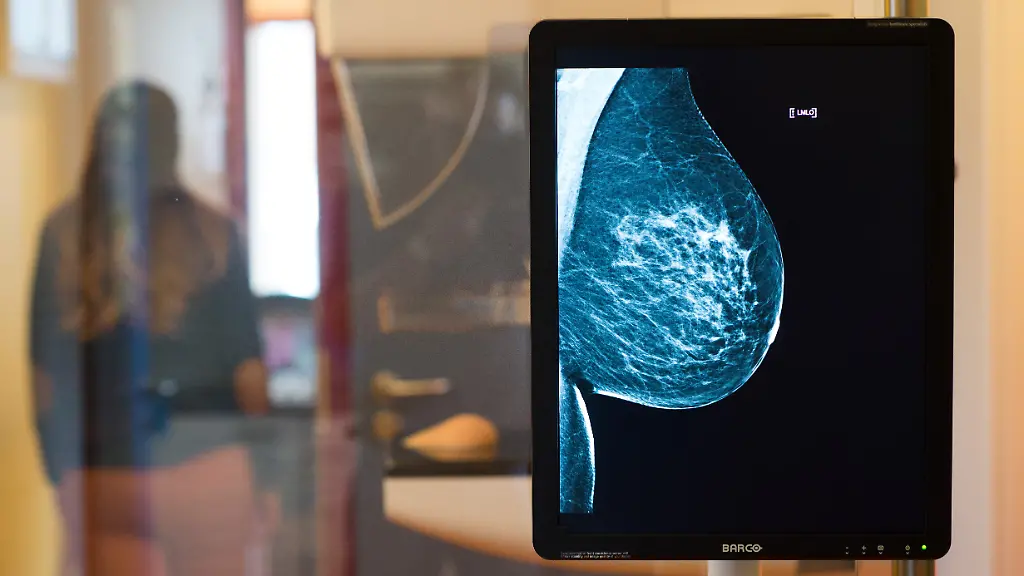

Andere Verfahren als MammografieWas ist die beste Brustkrebs-Früherkennung?

Die Mammografie soll beim Brustkrebs-Screening gefährliche Tumore möglichst frühzeitig aufspüren. Oft jedoch gelingt das nicht. Studien deuten darauf hin, dass andere Verfahren besser sind.

Die Brustkrebs-Früherkennung, zu der in Deutschland Frauen zwischen 50 und 69 Jahren alle zwei Jahre zur Mammografie eingeladen werden, soll gefährliche Tumore zeitig aufspüren. Dass das oft nicht gelingt, zeigen die sogenannten Intervallkarzinome: Das sind Tumore, die nach einer unauffälligen Früherkennungs-Mammografie diagnostiziert werden, etwa weil sie durch Tastbefund auffällig werden. "Ein Intervallkarzinom ist ein Indiz für eine gescheiterte Früherkennung", sagt Christiane Kuhl von der Uniklinik Aachen.